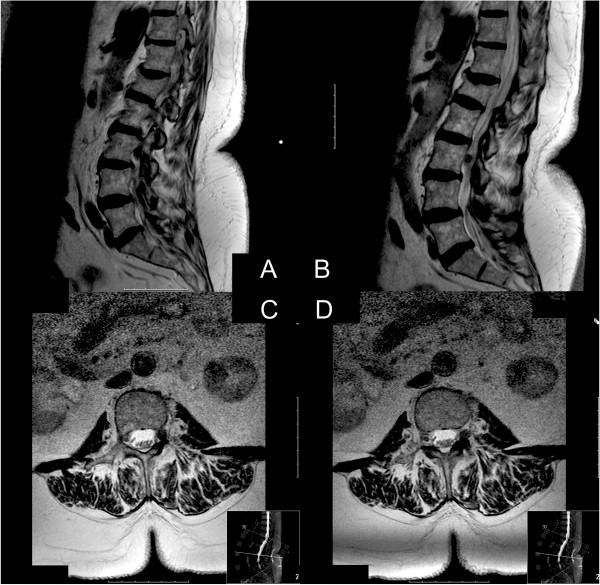

A 70-year-old Caucasian woman with a four-month history of left-sided lumbar radiculopathy was admitted to our department under the assumption of a herniated lumbar disc. Her past medical history included a pulmonary adenocarcinoma and invasive ductal breast cancer.Lumbar magnetic resonance imaging revealed a space-occupying mass in her left neuroforamen L3-L4 with compression of her L3 nerve root. Neurinoma was taken into account as a differential diagnosis, although not considered typical. Surgery revealed a metastasis of pulmonary adenocarcinoma to her dorsal root ganglion.

一名70岁的白人女性,有4个月左侧腰神经根病病史,因疑似腰椎间盘突出症入住我科。她既往有肺腺癌和浸润性导管乳腺癌病史。腰椎磁共振成像显示其左侧L3-L4神经孔有占位性肿块,压迫L3神经根。考虑到神经鞘瘤作为鉴别诊断,尽管并不典型。手术发现肺腺癌转移至其背根神经节。